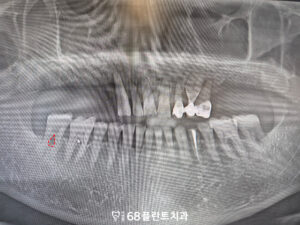

또한 오른쪽 아래 맨 뒤 치아는

맞닿는 위 치아가 없어

점점 정출되어 올라온 상태였습니다.

대합치가 없는 상태가 오래 지속되면서

해당 치아가 위로 자라 나오듯 이동하였고,

그로 인해 교합 평면이 흐트러진

모습이 확인되었습니다.

그리고 해당 치아 역시

치주염의 영향으로

치근분지부까지 골 소실이

진행된 상태였습니다.

그래서 발치 후 철산역임플란트를

함께 식립하기로 계획을 수립하였습니다.

마지막으로 왼쪽 아래 치아는

오래 전 신경치료를 받은 이후,

위 보철을 씌우지 않고

치료를 중단한 상태였으며

그로 인해 치관부가

파절된 모습이 확인되었습니다.

신경치료를 받은 치아는 내부 수분이 감소해

상대적으로 취약해질 수 있는데,

보철 수복 없이 장기간 사용하게 되면

저작 압력에 의해 균열이나

파절이 발생할 가능성이 높습니다.

그래서 해당 치아도

발치 후 임플란트를 식립하기로 하였으며

전체적인 치료 계획을 전부 수립하였습니다.